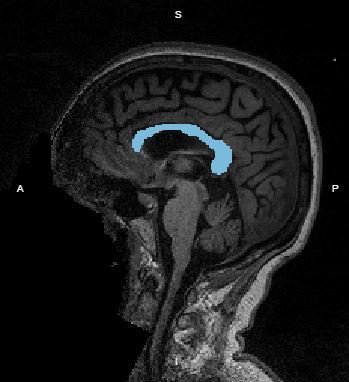

- Objectif : Comparaison de méthodes automatiques et de méthodes manuelles pour la segmentation du thalamus sur des IRM cérébrales

Circonstances : Expérience MAGNIMS

Outils utilisés :

- BrainBrowser

- Canvas HTML5

Visualisation simple d'une segmentation

Comparaison des segmentations

- Support : Canvas HTML

- Couleur : Format HSV

- Affichage : BrainBrowser